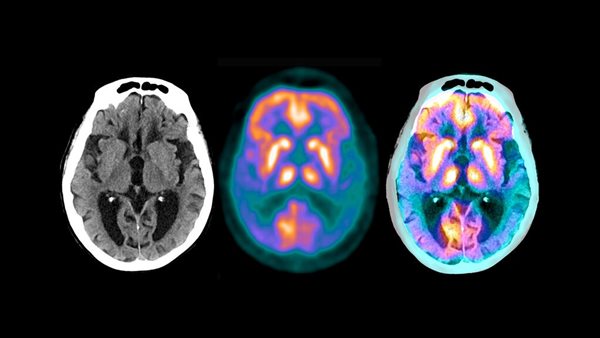

اشتملت الدراسة التي استمرت عامين على 272 مريضًا لديهم فحوصات دماغية تشير إلى مرض الزهايمر تراوحت أعراضهم من خفيفة إلى معتدلة.

المشاركون الذين تلقوا الدواء كان لديهم تباطؤ بنسبة 32 في المئة في معدل الانخفاض، مقارنة مع أولئك الذين حصلوا على دواء وهمي. قال الدكتور دانيال سكوفرونسكي، كبير المسؤولين العلميين في الشركة، إنه في غضون ستة إلى 12 شهرًا، اختفت اللوحات وبقيت. في تلك المرحلة، توقف المرضى عن تناول الدواء - حصلوا على دواء وهمي - طوال مدة الدراسة.